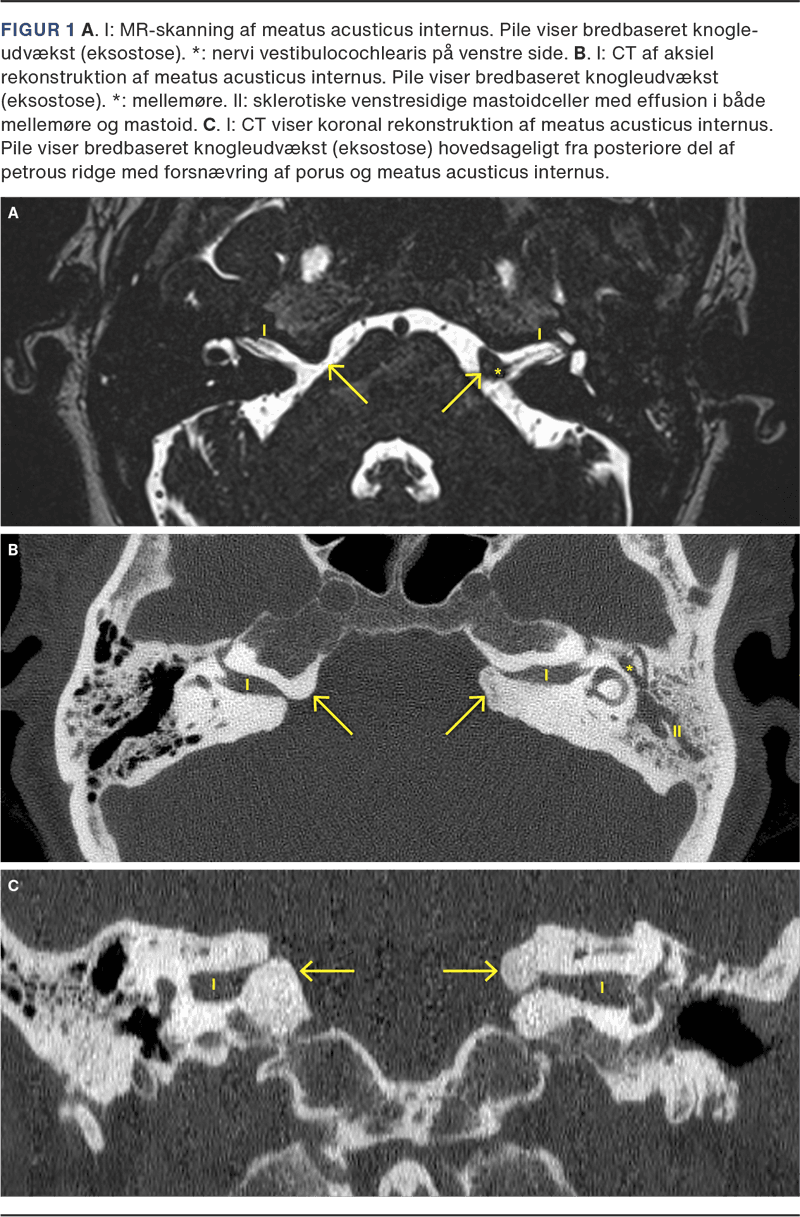

Som fireårig havde patienten haft et faldtraume, hvor hun fik kraniebrud og lå i respirator gennem noget tid. Patienten havde sequelae i form af hjerneskade og muligvis epilepsi som følge heraf. Der forelå ingen billeddiagnostik fra patientens barndom. I forbindelse med udredning af det perceptive asymmetriske høretab blev der foretaget MR-skanning, som viste bredbaseret knogleudvækst hovedsageligt fra den posteriore del af petrous ridge med forsnævring af IAC (Figur 1 A), hvor der sås masseeffekt og kontakt med nervus vestibulocholeraris på begge sider. Cochlea og buesystem sås normale bilateralt.

Supplerende CT af os temporale havde vist IAC-eksostose på begge sider (Figur 1 B + C) samt delvist sklerotiske venstresidige mastoidceller (II) med effusion i både mellemøre og mastoid.